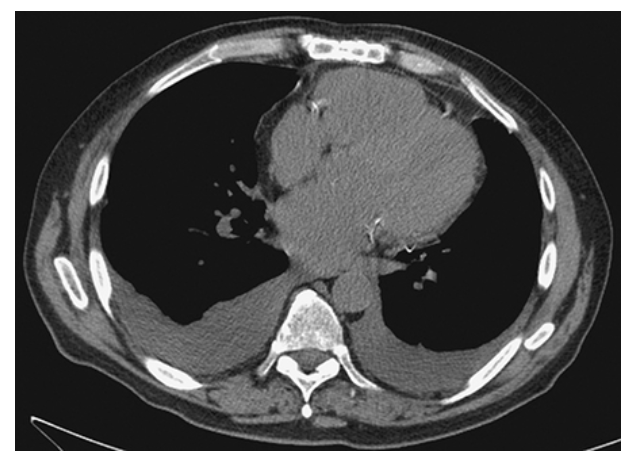

Pleural Effusion. CT with soft tissue windows shows fluid within the dependent pleural space bilaterally.